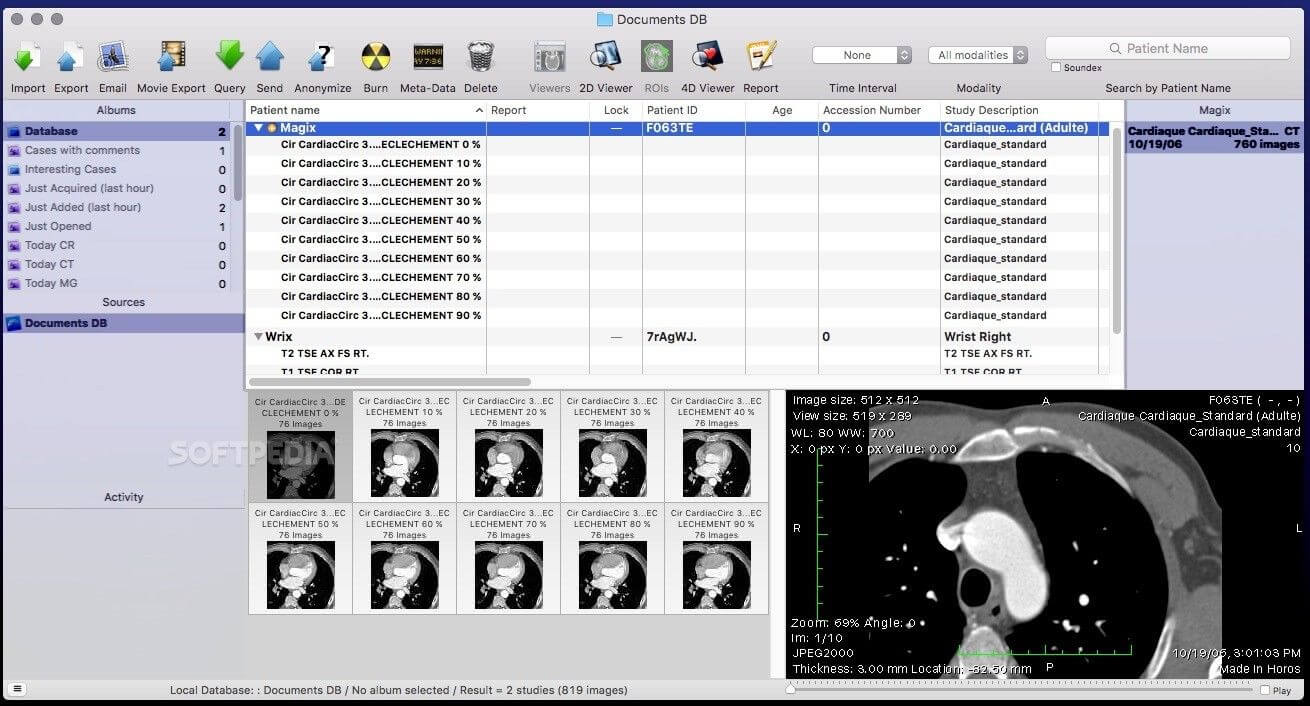

Horos is an open source DICOM viewer for Mac. It is actually the free version of an expensive DICOM viewer called Osirix MD, which is often considered to be the best DICOM viewer for Mac. It only runs on Mac OS, version 10.8 or higher. This software allows for most diagnostic techniques, including multiplanar reconstruction, maximum intensity projections, and volume rendering. It also has tools for manipulating images and making measurements.

One of the unique features of Horos is that it has a plug-in that allows uploading of images to Radiopedia, an online resource with a large number of reference cases and articles. Technical support is available through both phone and email. Horos, however, does not integrate to PACS free of cost. Cloud-based storage is available at an additional cost.

A free version of Osirix MD, called Osirix Lite, is also available to users. However, it does not allowing editing of imaging metadata, and image modifications come with a watermark. While this is good to get a feel for the parent software, it is not intended for regular medical use.